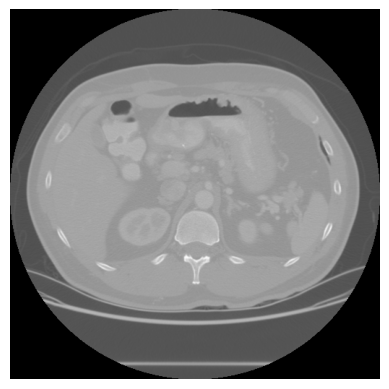

Para ter uma visão geral do volume, podemos exibir fatias espaçadas regularmente:

# exibir 5 fatias distribuidas ao longo do volume

n_fatias = ct_array.shape[0]

indices = [0, n_fatias // 4, n_fatias // 2, 3 * n_fatias // 4, n_fatias - 1]

fig, axes = plt.subplots(1, 5, figsize=(18, 4))

for ax, idx in zip(axes, indices):

ax.imshow(ct_array[idx], cmap="gray")

ax.set_title(f"Fatia {idx}")

ax.axis("off")

plt.tight_layout()

plt.show()

As fatias extremas (0 e 118) mostram pouca anatomia. Conforme avançamos para o centro do volume, pulmões, costelas e coluna vertebral aparecem com clareza.